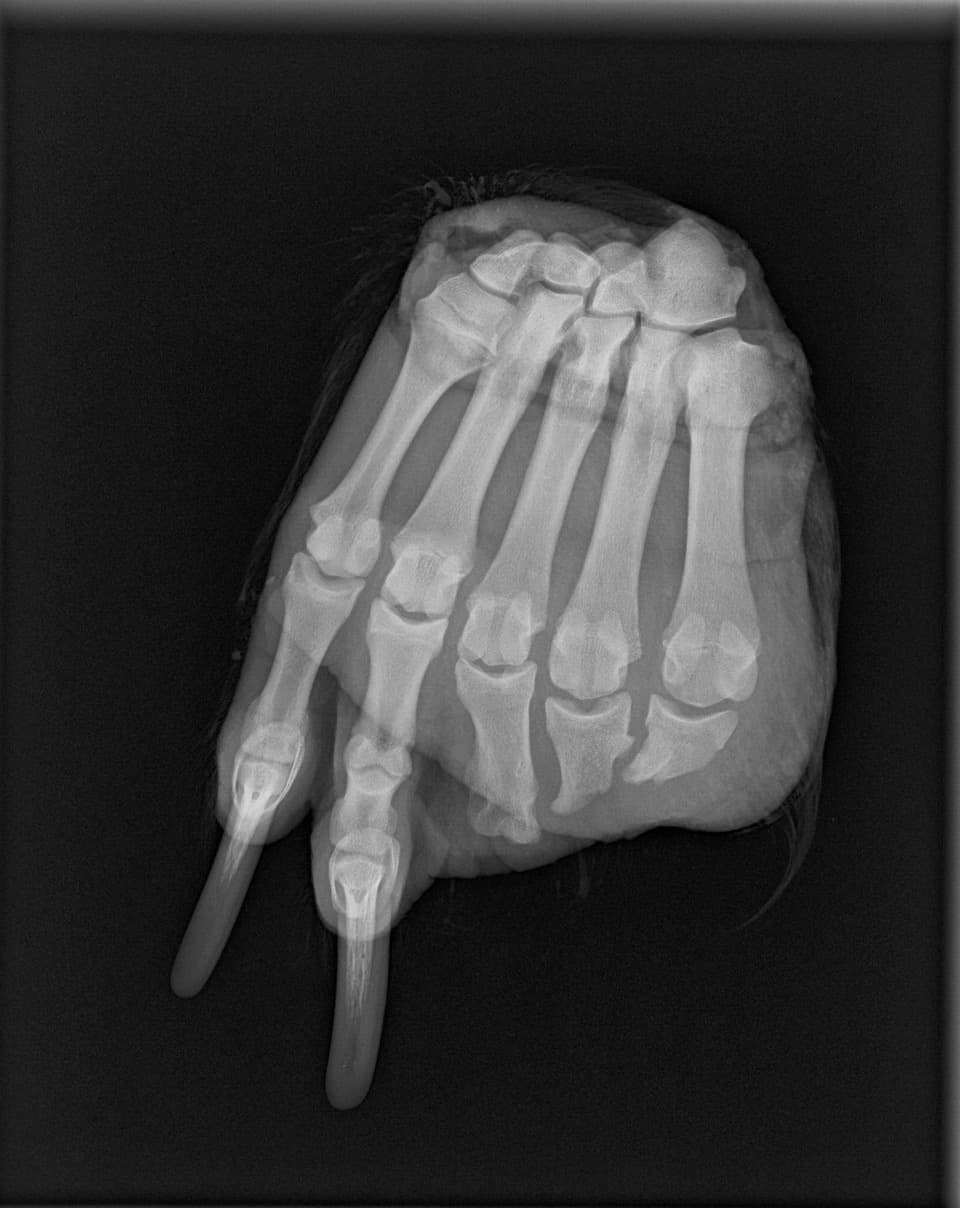

Lamb and his team discussed the situation with wildlife veterinarians. They ruled out birth defects or exposure to some type of toxin. Then, they had one of the feet x-rayed and saw that it was a straight break. The team considered that maybe the bears were getting their feet caught on the railway and getting run over by a train. But all of the bears had way too similar breaks and only on their front feet. When the researchers discussed the issue with trappers and hunters, they learned that bears had been getting caught in small traps often set for weasels, martens and other furbearers.

Some people suggested that better anchoring the traps so bears can pull out their toes instead of carrying away the traps could help, but when Lamb and his team tested this theory by placing a dead grizzly’s leg into a better anchored trap, they found it wasn’t always easy to pull the leg out.